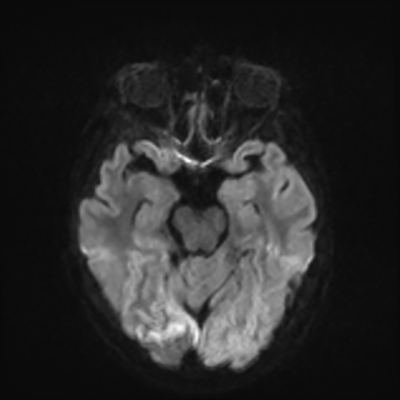

MRI brain (DWI)

MRI brain (DWI) 3/24 3/24

You can clearly see diffuse cortical and basal ganglia diffusion restriction, and that of his deep cerebellar nuclei as well. The right occipital lobe abnormalities are a little more prominent, but then you remember that he is known to have had a right occipital stroke weeks ago.

In reviewing his data, you know that he doesn't have any of the strong predictors of a poor neurologic prognosis. However, based on these findings on MRI, along with the absent reactivity on cEEG, you are able to tell the primary team and the patient's family that he is likely to have a poor prognosis, based on these multiple moderate predictors. Recovery is not completely impossible-- there is more uncertainty with this prognostication than if we were able to get SSEPs-- but you're very worried about his outlook and that any potential recovery would require a very protracted rehabilitation period. Given his high cervical cord injury level, tracheostomy would be required anyway. So, it comes down to whether his family thinks he'd want to pursue these aggressive measures.